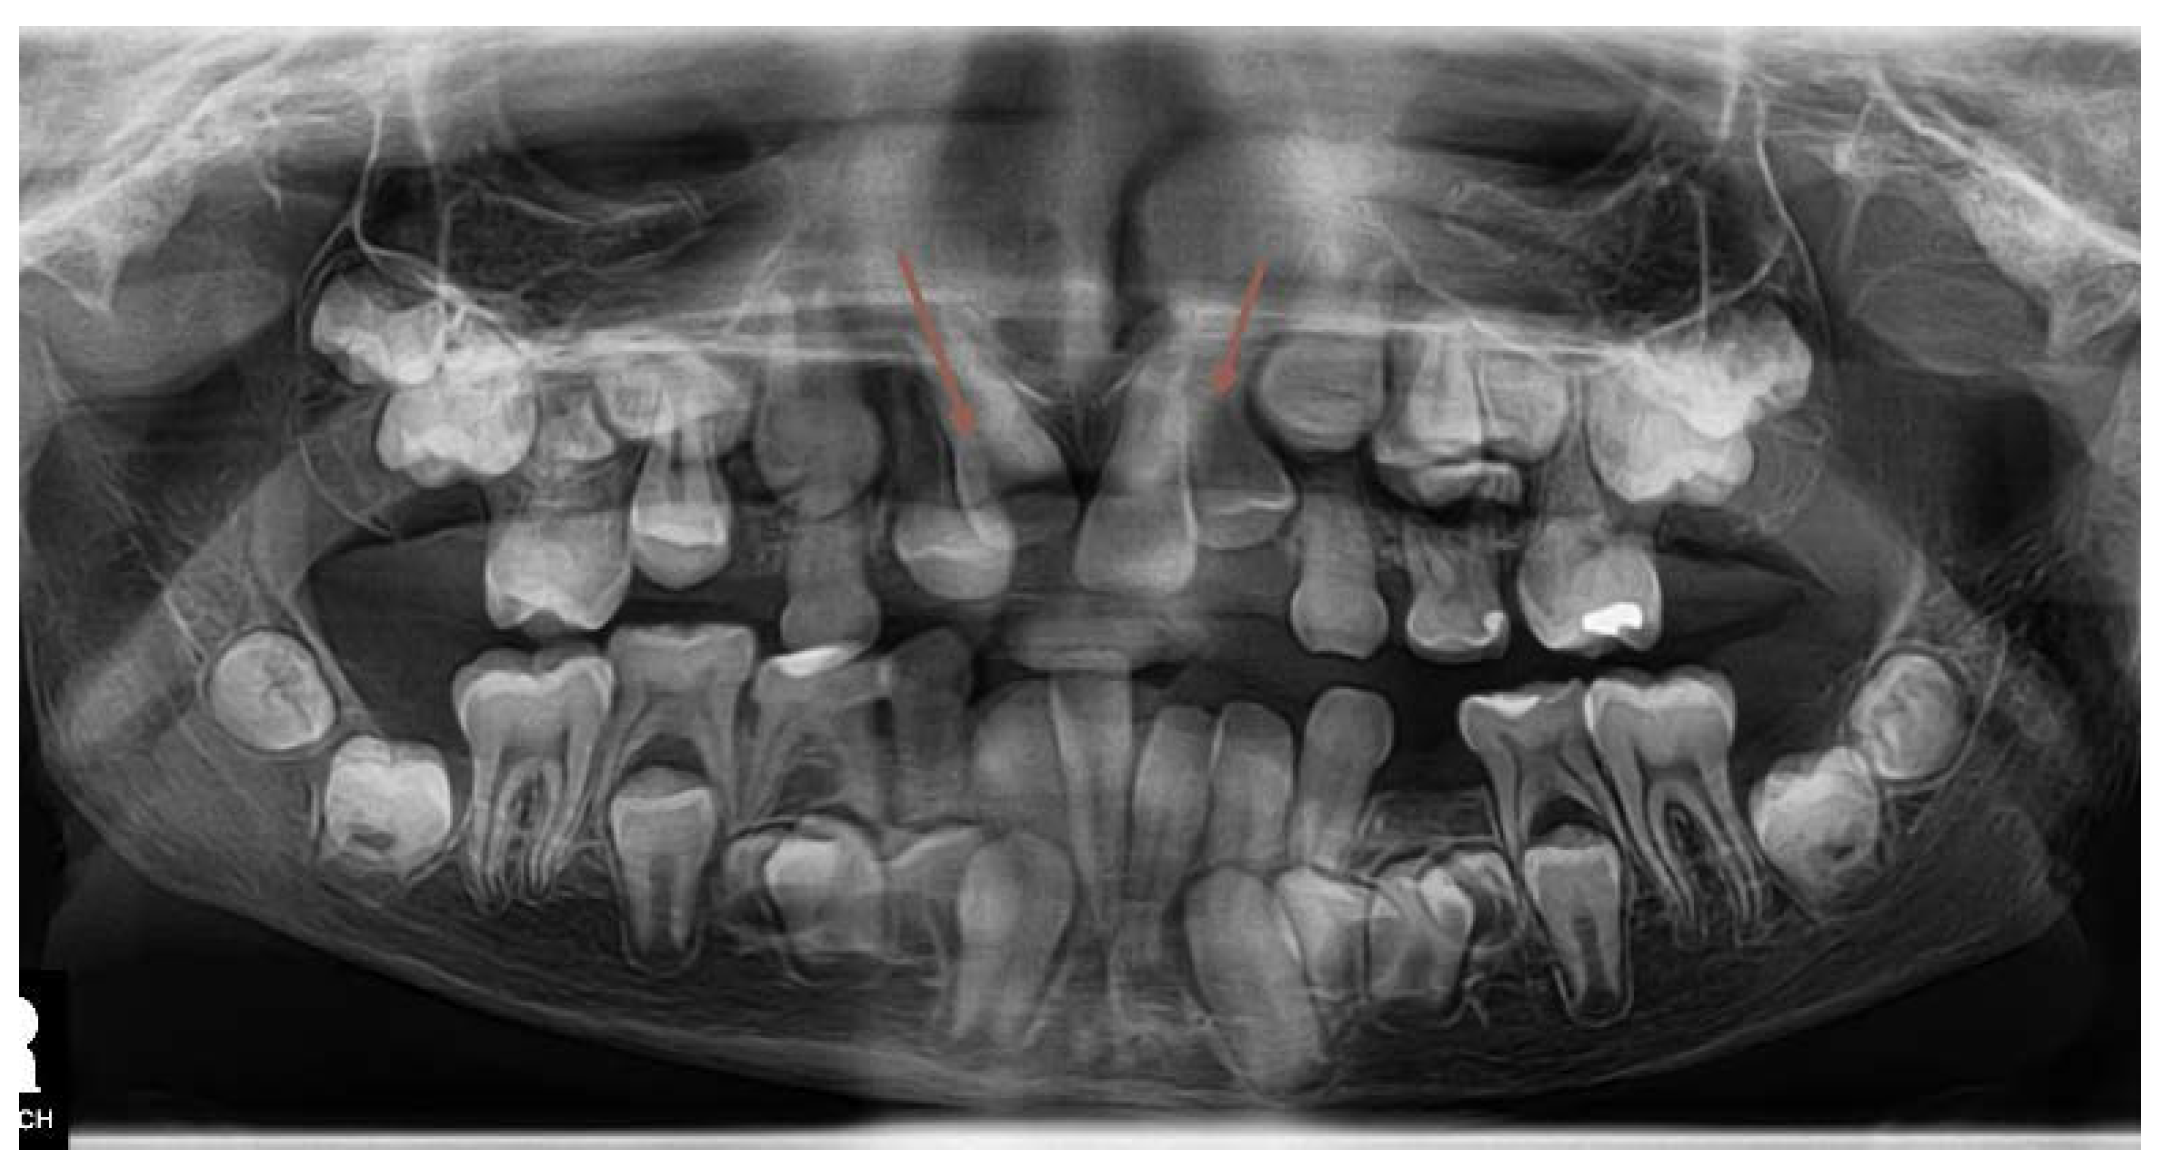

Fixed Appliance Orthodontic Treatment- Phase 2

A new OPG x-ray was taken in November 2022 (Figure 17). The upper incisors were in place and their roots were fully matured. The 45 was already in the correct position, the 35 was in a slightly crowded position, but the lower canines cooperate well with the orthodontic forces. But at this time was already clear, that newly formed supernumerary teeth started to mineralize their crowns in the upper alveolus, two in the upper right and one in the upper left quadrant. (Figure 17). It was necessary to plan a third surgical intervention under general anesthesia.

Figure 17. Three supernumerary teeth emerged on the OPG x-ray in the upper arch. .